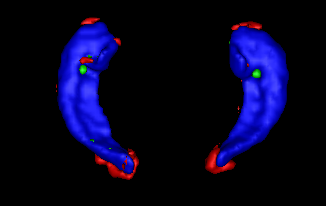

Estimator maps for several features and several patch sizes are shown in Figure 7, for a subject of the EADC-ADNI dataset. First, bigger patch sizes produce smoother estimator maps. Smaller patches are able to better capture finer details at the expense of noisier estimator maps. Second, the estimators based on gradient norm better define edge structure but are less robust to noise. Finally, the aggregation is able to produce a good trade-off between considered scales and features.

Figure 8 presents segmentation results of best, median and worst subjects obtained on the EADC-ADNI dataset. First, we can see that automatic method produces a smoother segmentation than expert. The patchwise label fusion obtains consistent segmentation along the edge, but tends to fill holes present in manual segmentation. Some of these holes appear to be hippocampal CSF while others seem to be expert inaccuracies.